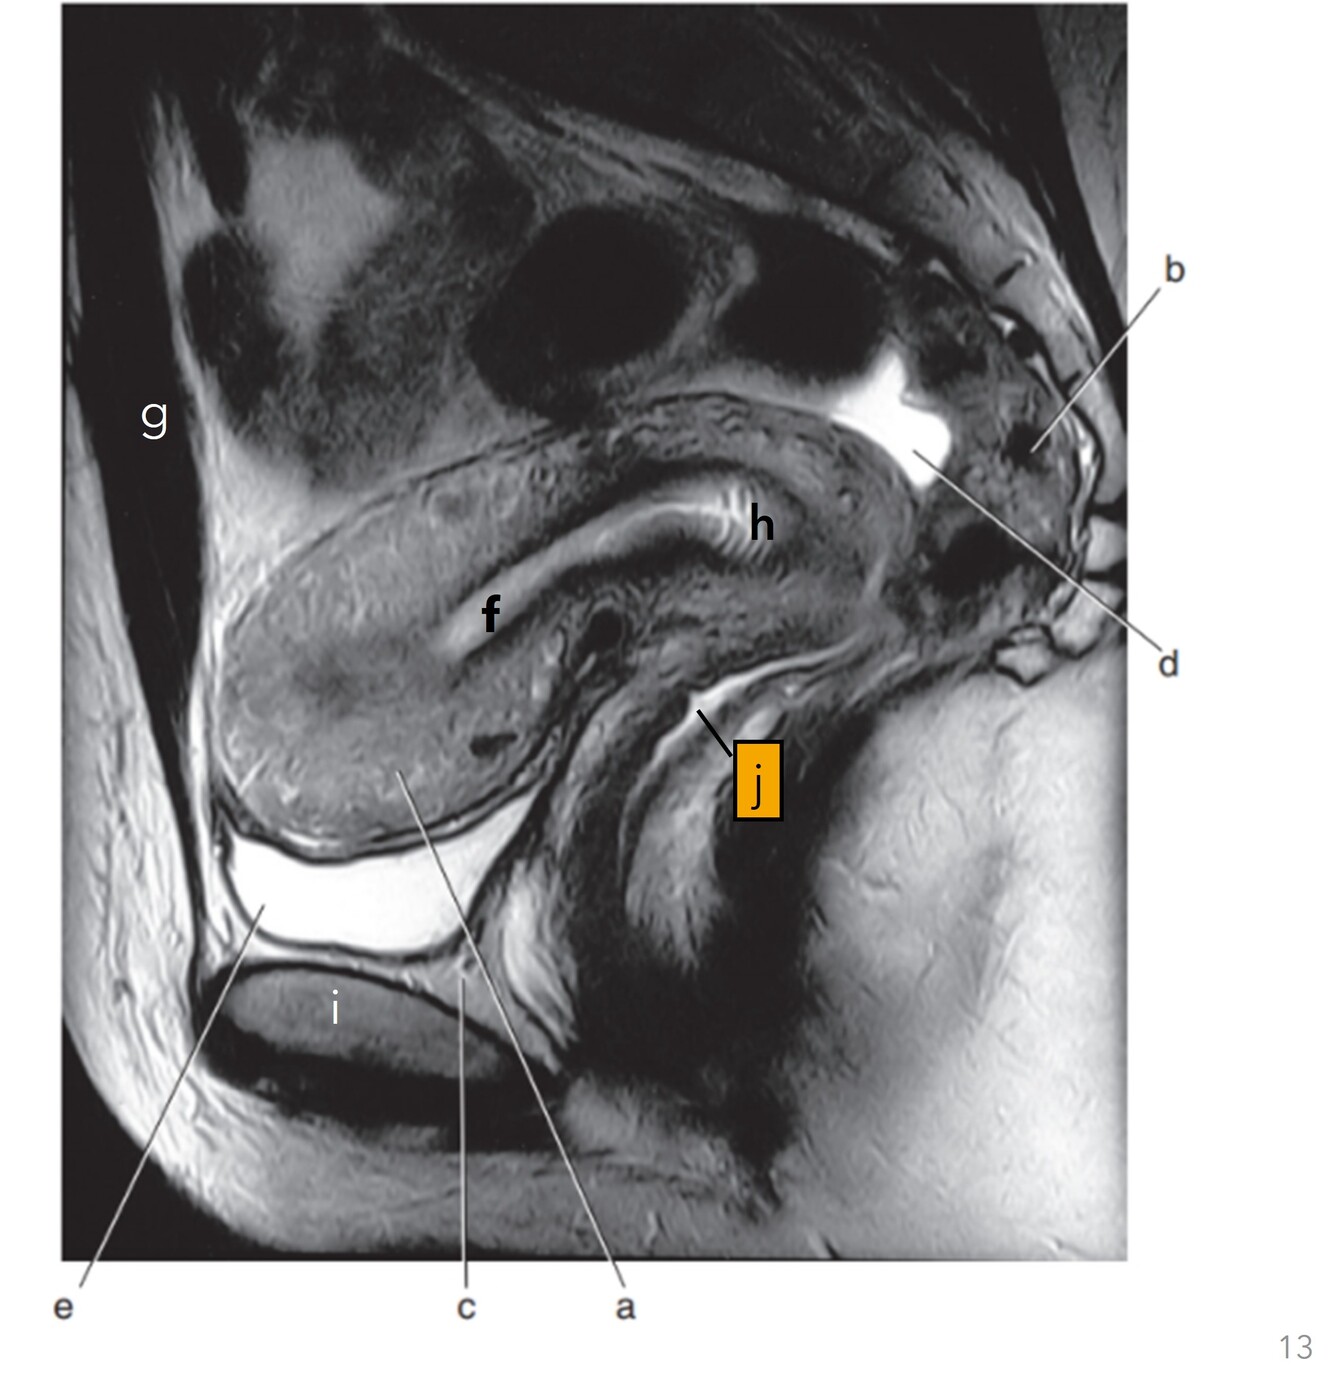

13

Q

Label a-e

A

a. Myometrium (uterus)

b. Rectum

c. Retropubic space

d. Pouch of Douglas/Rectouterine space

e. Bladder

14

Label f-j

f-Uterine cavity

g-Rectus abdominis

h-Cervix

i-Pubis symphysis

j-Vagina